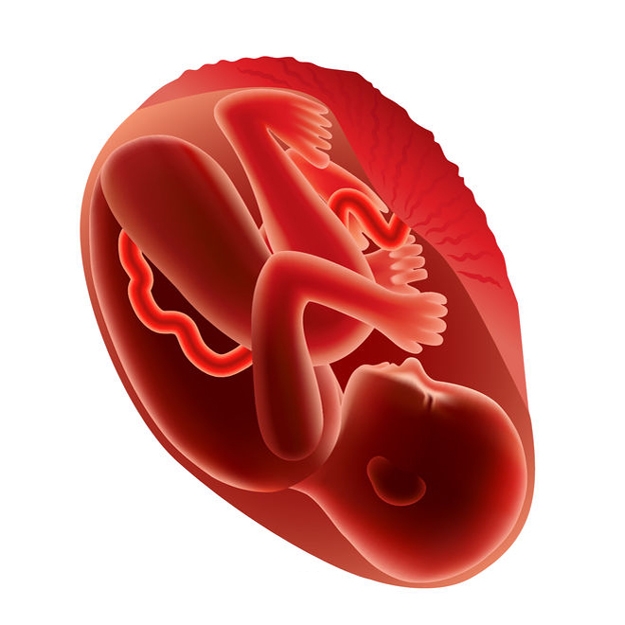

All About 36 Weeks Pregnant – Stomach, Body, Fetus, Diet, And Development

Pregnancy – Stages of Fetal Development – American SPCC